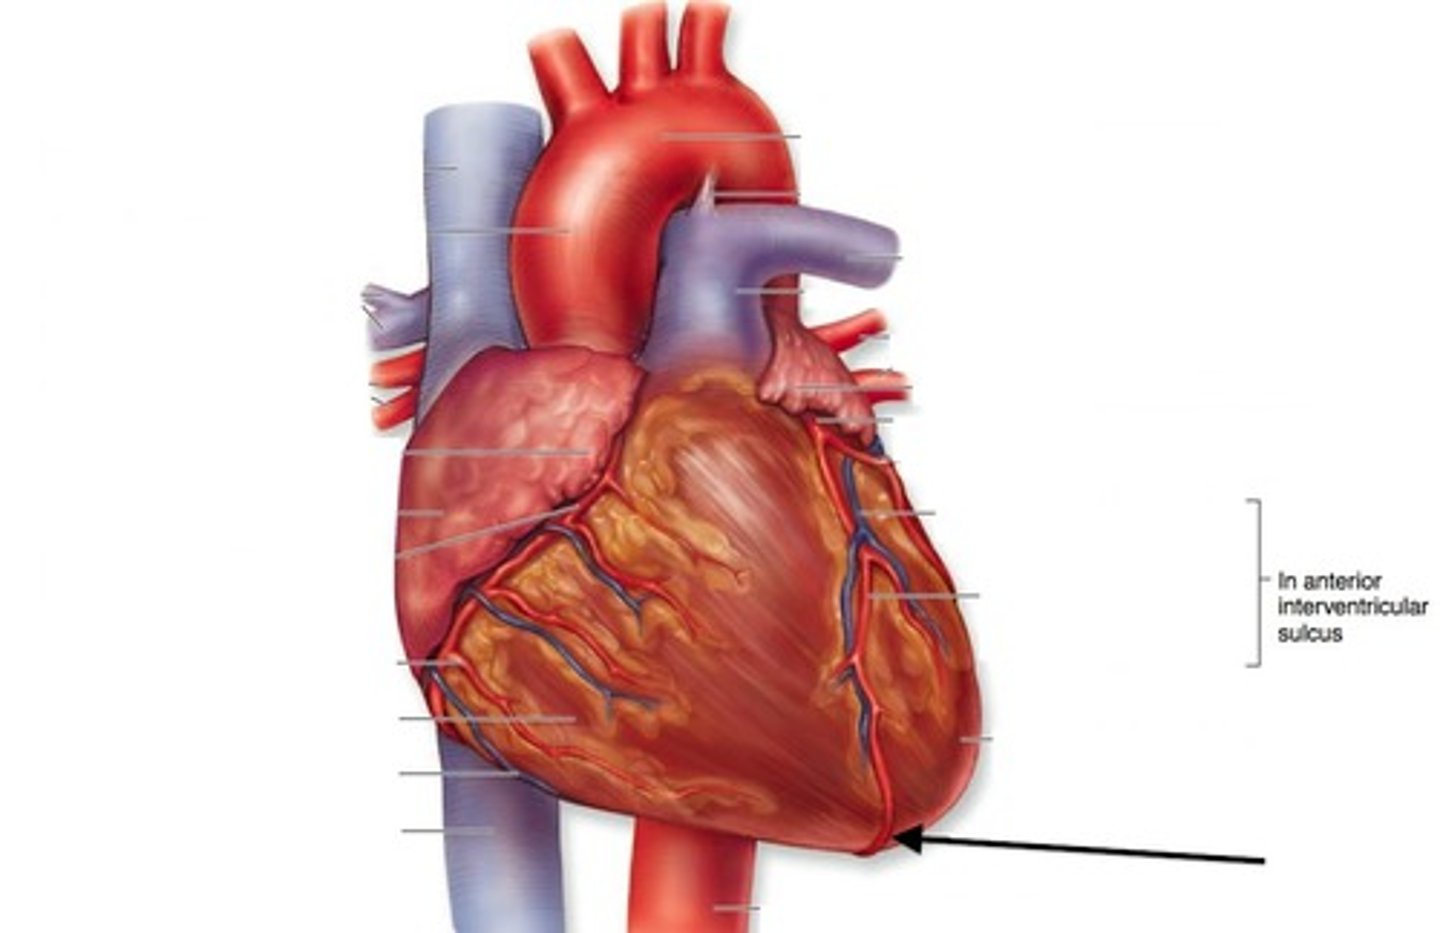

anterior interventricular sulcus

depression. anterior of the heart.

Left anterior descending artery

Structure. In the anterior interventricular sulcus.